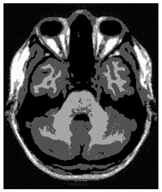

Figure 9 shows a magnified view of the segmentation results of slice 90 of the BrainWeb dataset, compared with the ground truth image. It can be observed that for complex edge areas, both Cauchy-TB and the Tsallis-BE method outperformed the Otsu method. They could clearly and accurately delineate the target region with fewer misclassifications. However, the Tsallis-BE method showed over-segmentation in edge details, where some background pixels were erroneously classified as foreground, leading to differences from the ground truth in the edge contours. Cauchy-TB represented an obvious improvement in this aspect.

Figure 9.

Enlarged images of the segmentation results of slice 90 in BrainWeb with three methods.